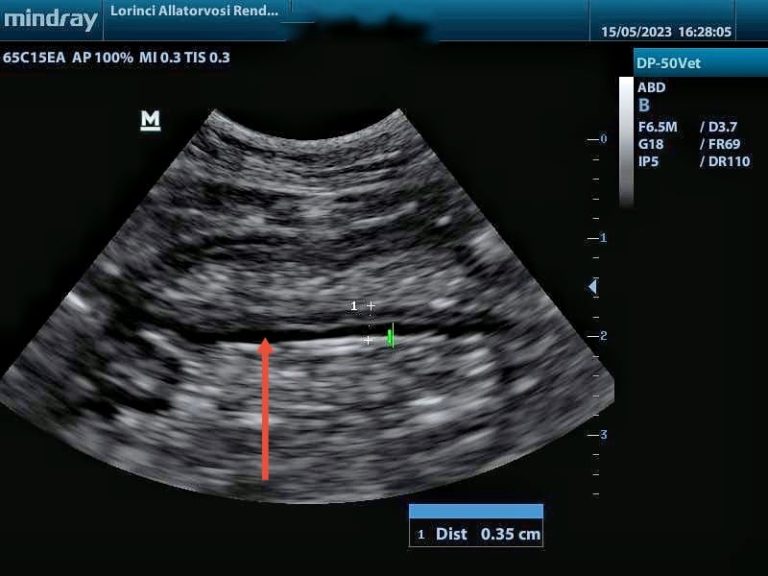

Hasi ultrahang vizsgálat során hasonló elváltozásokat láthatunk mindkét betegségtípusnál. A gyomor és belek fala több rétegből áll és ezek eltérő mértékben vastagodhatnak meg a különböző betegségekben. Limfóma esetén rendszerint az izomréteg, gyulladásnál általában a nyálkahártya válik vaskosabbá, de sajnos ez nem minden esetben történik így, különben könnyű lenne a gyulladásos és daganatos folyamatokat elkülöníteni egymástól.

Gyulladás miatt megvastagodott izomréteg